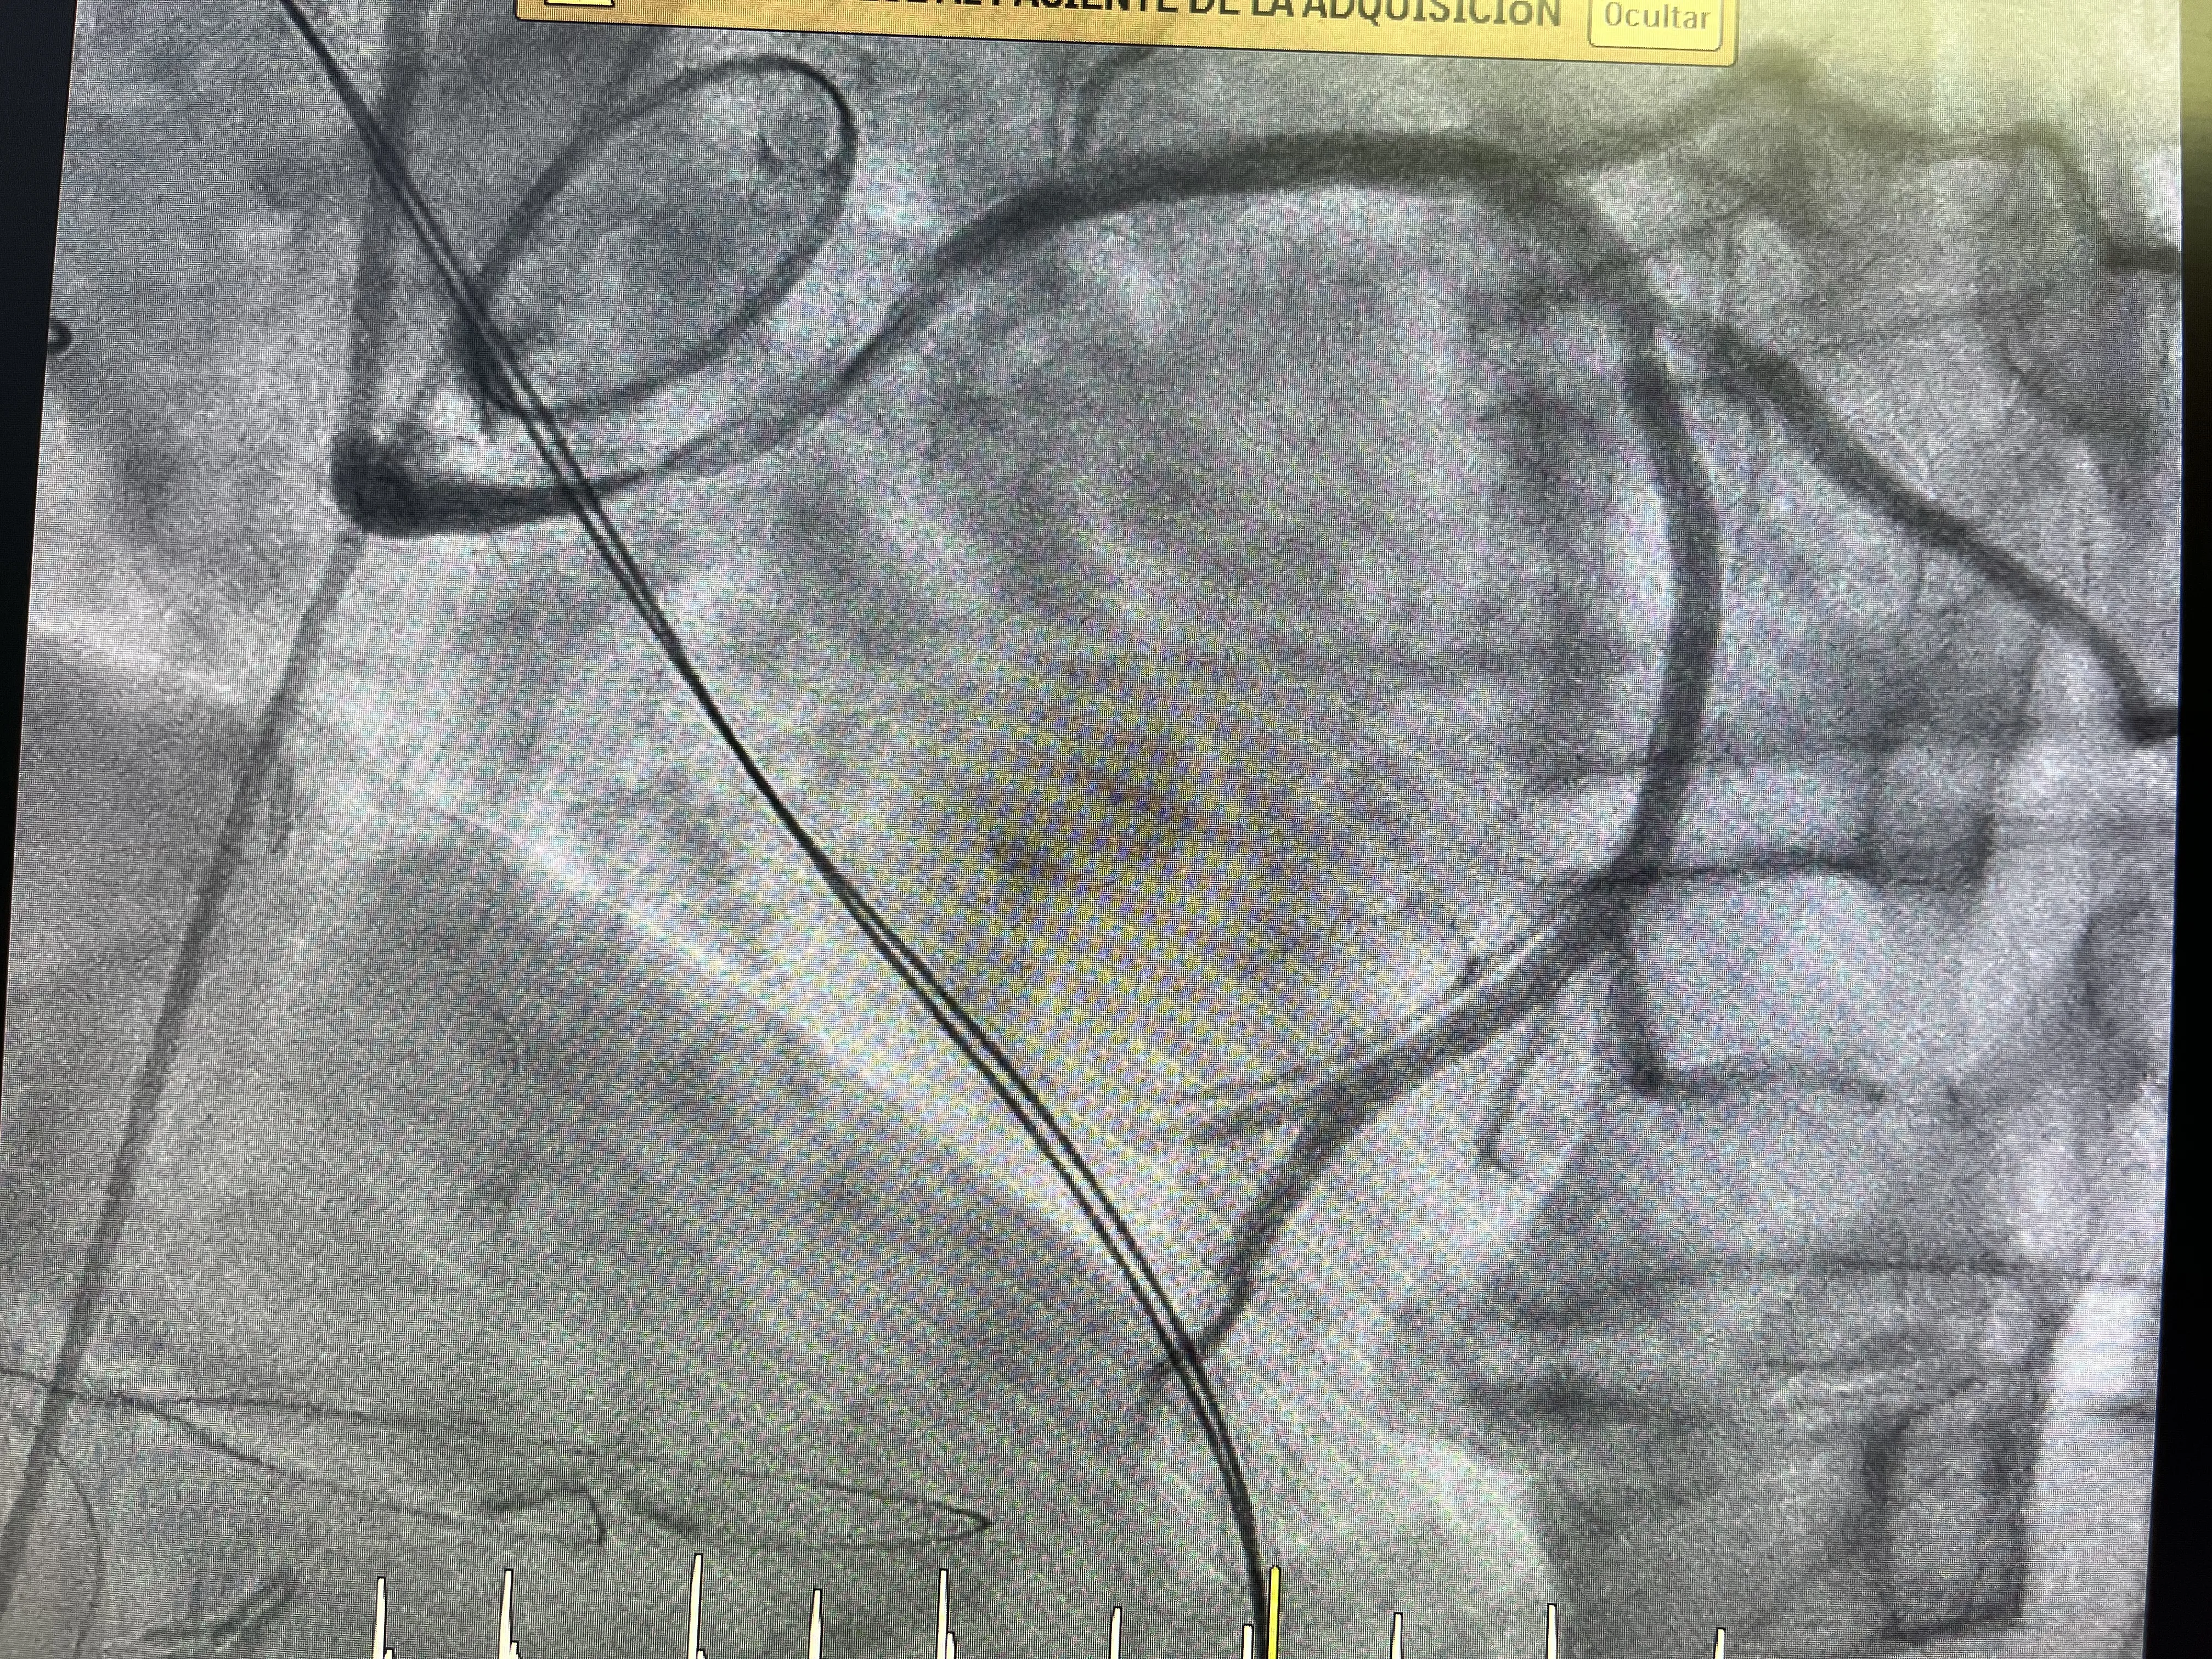

Tras la predilatación, se observa una mejoría en el paso de contraste, lo que indica que la arteria puede mantenerse abierta si se le da un soporte estructural. En ese punto se decide implantar un stent en la circunfleja, con el objetivo de mantener el vaso expandido y evitar una nueva oclusión. La colocación del stent en este contexto no solo trata una estenosis, sino que compensa el efecto de la sutura que había estrangulado la arteria. Es una solución percutánea a una complicación mecánica generada en quirófano.

El resultado de la angioplastia con predilatación y stent es la recuperación del flujo coronario hacia el territorio de la circunfleja. Con ello, se espera que la isquemia disminuya y que la situación hemodinámica del paciente mejore progresivamente. Este desenlace muestra cómo, incluso en un caso tan complejo, la combinación de cirugía cardíaca y cardiología intervencionista puede rescatar una situación crítica. El caso real de estenosis circunfleja queda así resuelto desde el punto de vista coronario, aunque el impacto del infarto dependerá del tiempo de isquemia y de la reserva miocárdica previa.